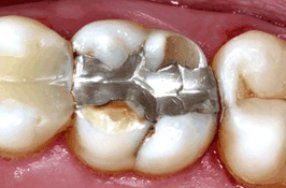

8. Ατελή σφραγίσματα ή θήκες δοντιών. Μετά την ολοκλήρωση μιας απονεύρωσης ακολουθεί η αποκατάσταση του δοντιού, η οποία πραγματοποιείται με σφράγισμα ή με θήκη ανάλογα πάντα με την έκταση της οδοντικής βλάβης. Δεν είναι λίγες οι φορές που μετά από χρόνια το σφράγισμα ή η θήκη που καλύπτει το απονευρωμένο δόντι επανατερηδονίζεται με αποτέλεσμα να μολύνεται από κάτω εκ νέου και η ήδη υπάρχουσα απονεύρωση. Τότε το δόντι πονά και είναι απαραίτητη η επανάληψη της απονεύρωσης και η νέα προσθετική αποκατάσταση του δοντιού.